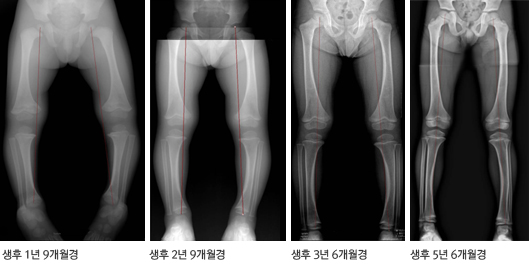

신생아는 약간의 내반슬을 가지고 태어났다가 성장하면서 3~4세경 외반슬이 되었다가, 이후 점차 감소하여 6~7세경부터 약간의 외반슬로 되어 성인에 이르게 되는데 3세 이전에 보이는 약간의 내반슬은 정상적인 발달 과정이다. 유아기 경골 내반증은 근위 경골(정강뼈) 성장판의 국소적인 발육 장애로 인해 발생하며, 초기 단계에서는 생리적 내반슬과의 감별이 어려울 수 있다. 환자의 나이, 방사선 사진에서의 변형 정도, 체중에 따라 보조기 치료나 수술적 치료를 하게 된다. 구루병일 경우에도 내반슬이 나타날 수 있다. 생후 6개월 이상인데도 모유만 수유하거나 아토피 등으로 극단적인 편식을 하는 경우에 발생하는 영양 결핍성 구루병, 그밖에 유전자 결함에 의해 발생하는 구루병이 있다. 외상 후 외반슬은 근위 경골의 골간단(뼈몸통끝, 뼈의 길고 곧은 주요 부분인 골간과 뼈의 끝 부분인 골단 사이의 부위)에 골절 이후 발생하는 것이다. 외상 후 일 년경에 가장 심해진다.